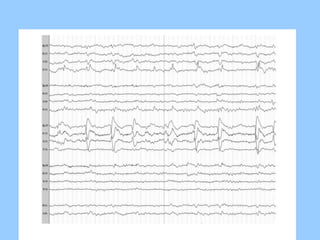

1. The document discusses EEG patterns and findings in various neurological conditions seen in children. It includes descriptions of normal EEG findings as well as abnormal patterns seen in conditions like absence seizures, West syndrome, benign childhood epilepsy with centrotemporal spikes, Lennox-Gastaut syndrome, non-convulsive status epilepticus, subacute sclerosing panencephalitis, and herpes encephalitis.

2. Case studies are presented with clinical histories and EEG findings to illustrate different pathologies. Treatment options are also mentioned for many of the conditions.